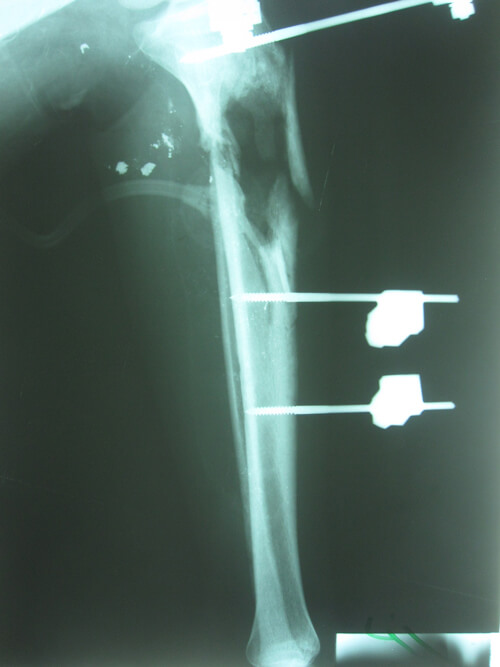

A 20-year-old man presented 46 days after a GSW injury to his right leg. He sustained a Gustilo IIIc fracture of the proximal tibia and fibula with division of the popliteal artery (Figures 13 & 14). The vascular defect was bridged acutely with a vein graft by a vascular surgeon. All toes were necrotic from either acute ischaemia or embolic injury. All compartments below the knee had been affected during the acute ischaemic episode. There was no neural function below the knee: the patient had an insensate foot with a pressure sore on the heel. This equated to a poor foot on an ‘almost dead’ stick.

Figure 14: Bone loss in the proximal tibial metaphysis.